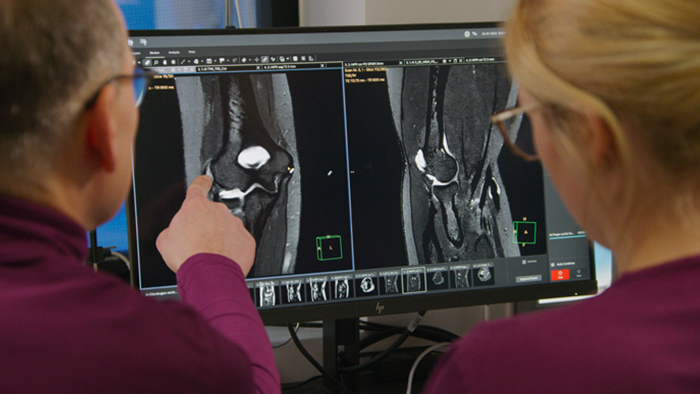

A future-focused subscription model providing continuous access to the most up-to-date MRI software.

Philips MR Subscription helps you realize the full potential of your MRI systems. Expand your clinical excellence, advance your operations and maximize your lifetime, so your team never falls behind.

Imaging departments have difficulty keeping up with the latest MR technology. Strained resources may leave them poorly equipped to respond to a variety of clinical needs and provide the best care to patients.

MR Subscription offers different modules to tailor your subscription to your needs. Choose the Speed module to enhance productivity with applications that support fast scanning and rapid diagnosis, without compromising image quality. Choose the Clinical module(s) to boost clinical confidence and flexibility with a breadth of advanced applications. Both modules provide access and clinical support for the most up-to-date Philips MR applications. With one transparent, predictable cost model, you can feel certain your department is prepared for any referral.